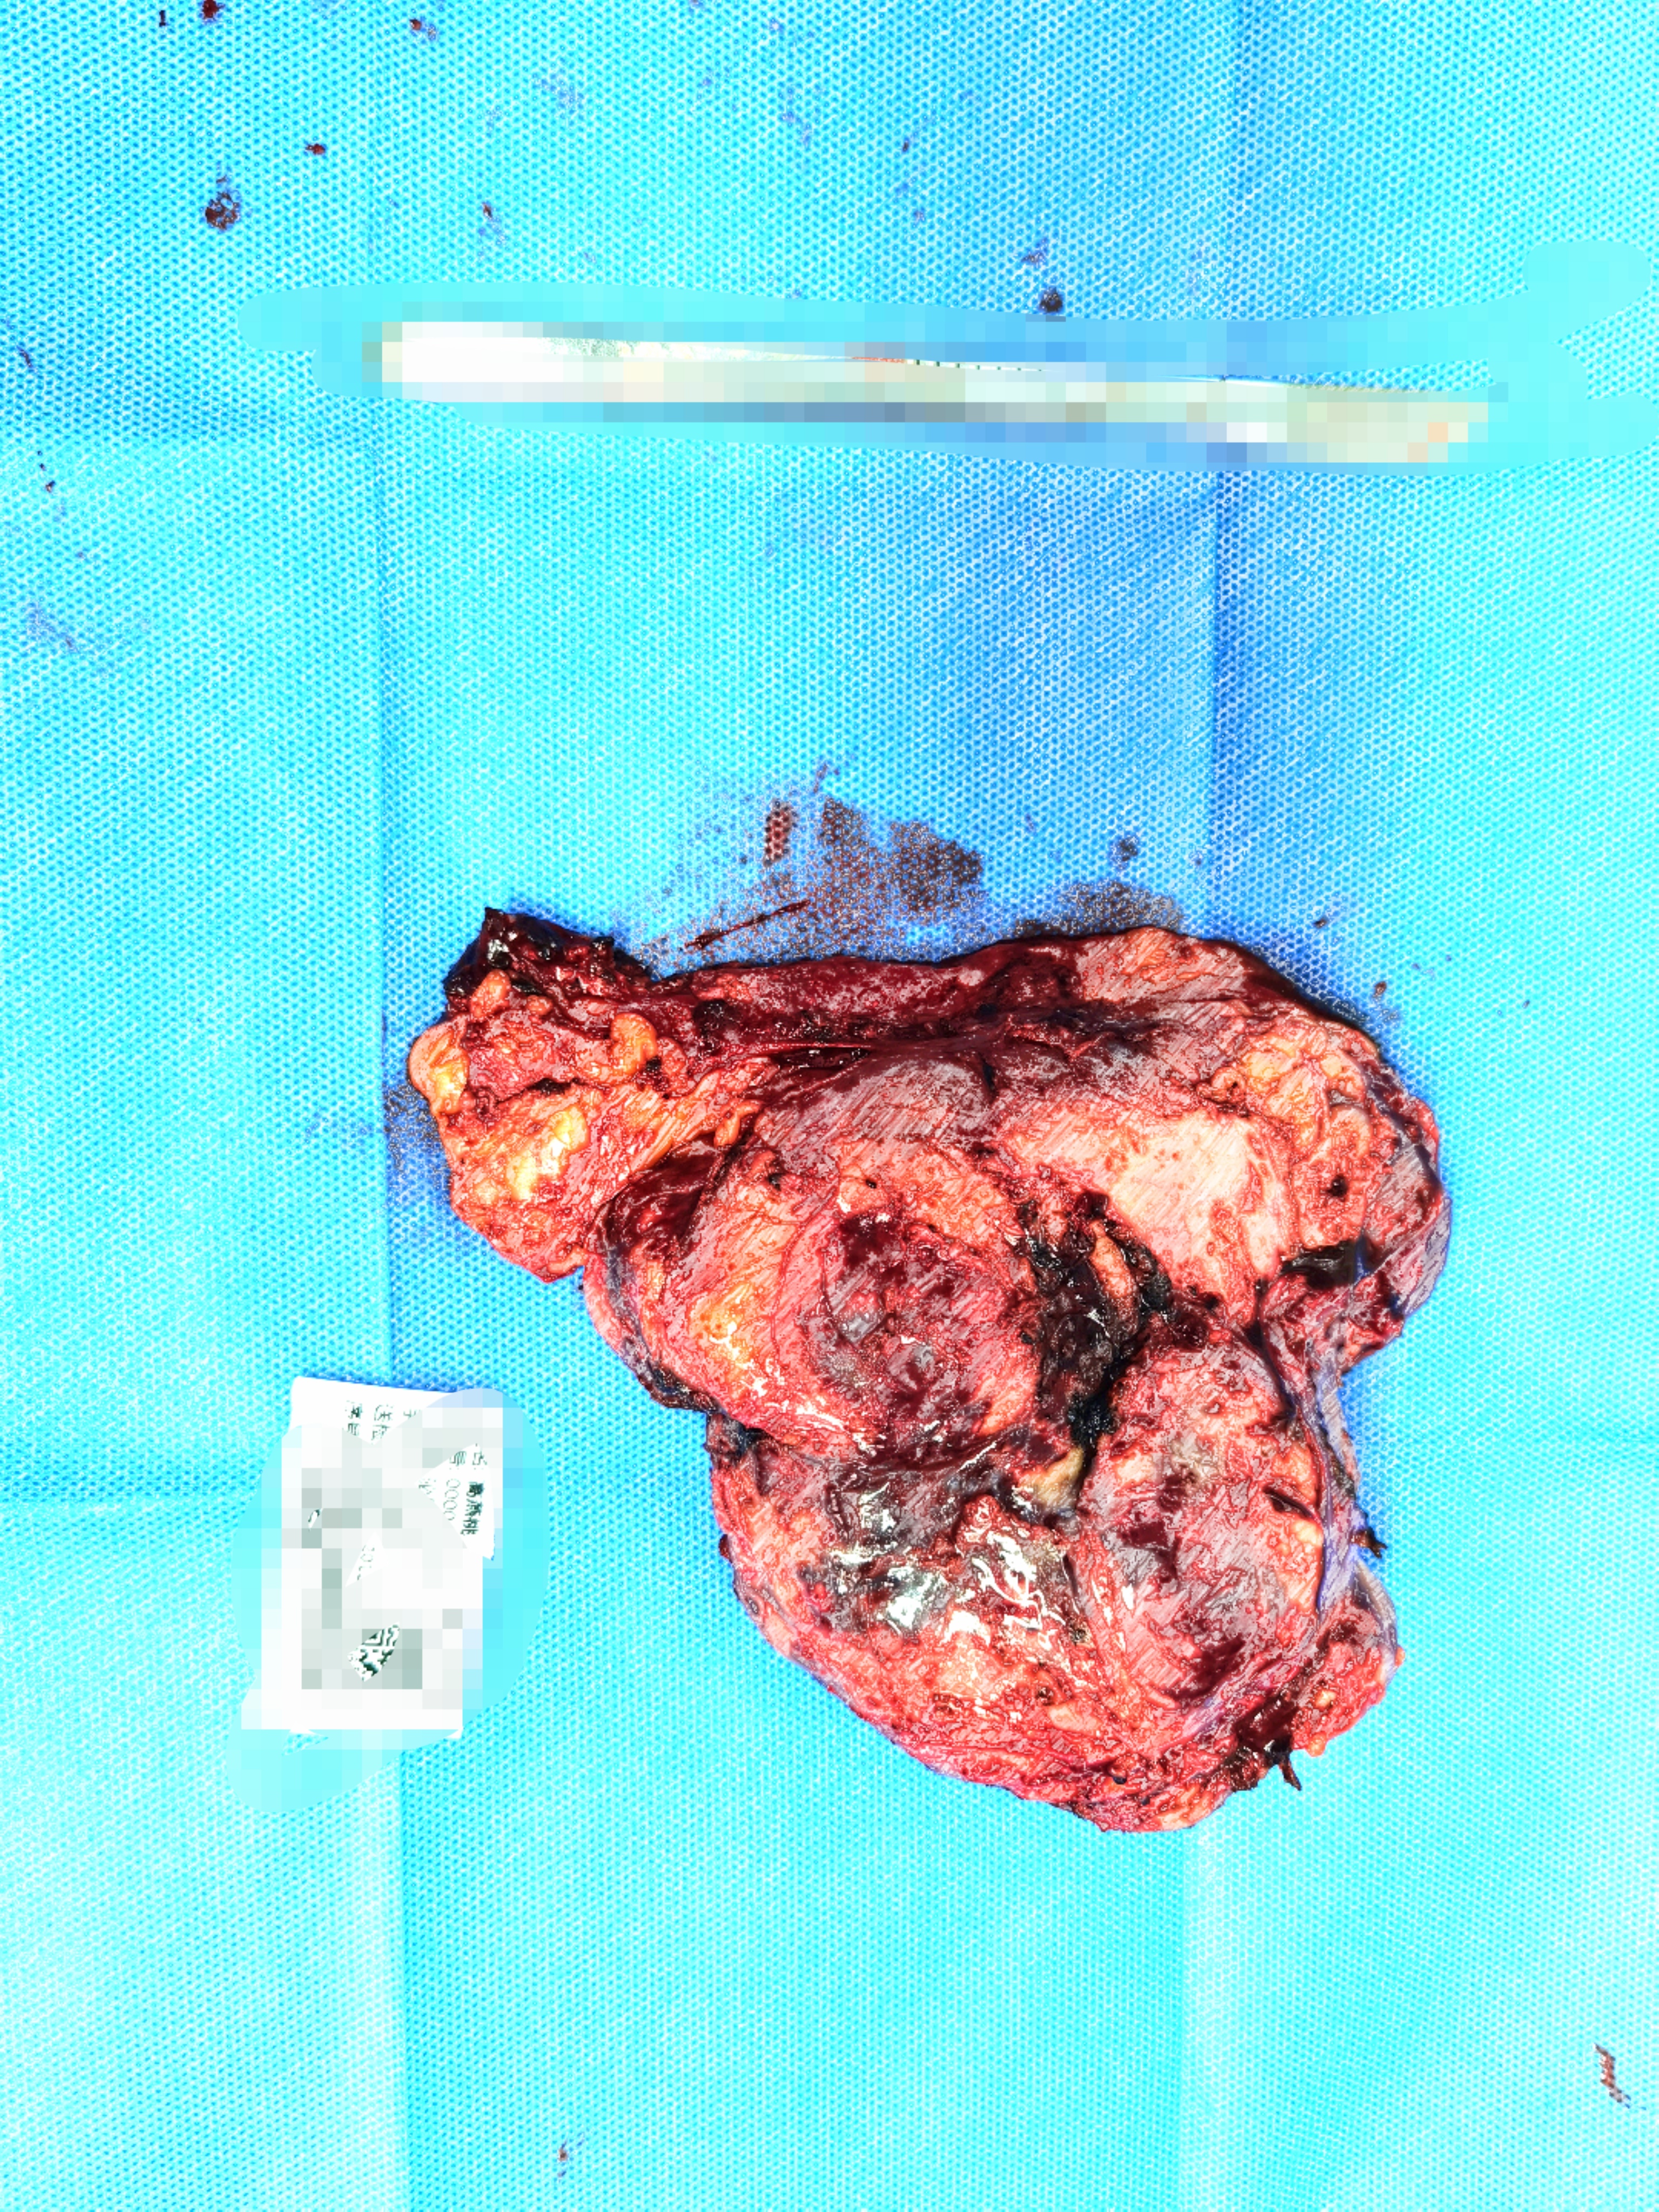

肿瘤缩小了,没有压迫到周围重要血管和器官,手术完整R0切除肿物,达到了无瘤状态(我心里也默默的给医院MDT团队鼓掌)。预计该术后不需要继续用药,患者定期进行复查即可以维持正常的生活了。

治疗后缩小并切除的肿瘤